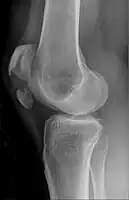

A fracture of the patella seen on a lateral view

A vertical patella fracture with the fracture line marked by a black arrow

Diagnosis is based on symptoms and confirmed with X-rays.[3] In children an MRI may be required.[3]